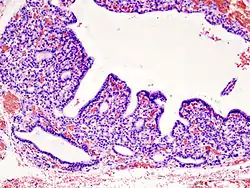

.jpg)